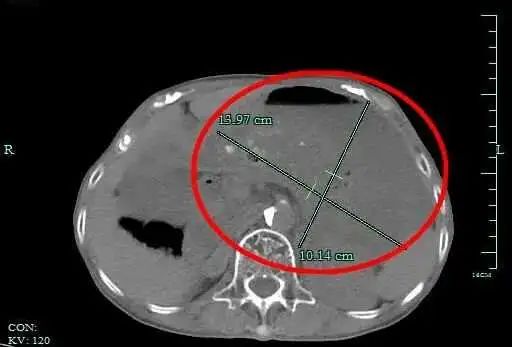

就这样吃了一个双休日,小丽感觉胃十分胀,上腹部还隐隐疼痛。难受得不行,小丽在家人陪同下,来到杭州市一集团瓶窑院区(余杭三院)就诊。消化内科孙国明医生接诊后,检查发现,小丽的胃里有大量没有消化的食物,胃腔比空腹状态扩大近40倍。

最后,小丽被诊断为“急性胃扩张”,入院治疗。所幸,经治疗后,小丽腹痛症状得以缓解,没有造成其他严重后果。

余杭三院消化内科主任段阳日介绍,我们的胃像一个具有超强伸缩能力的“储物袋”。在空腹状态下,成人的胃内容量约50毫升左右,拳头大小。正常进餐后,胃容量最大可以增大近30倍,约1500毫升。

但胃容量是有限的,如果一次吃太多东西,会使得胃壁各层膨胀比例不一,最里面黏膜层和其它层分离、缺血坏死,胃也就无法自行排空食物。 就好比一只气球,如果不断为其充气,达到极限时,气球壁就会变薄,并随时可能破裂。临床称之为急性胃扩张。